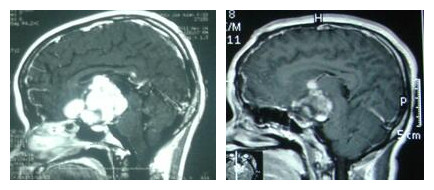

患儿,女,12岁,因“视力进行性下降2年,失明1年伴头痛呕吐2月,脑室腹腔分流术后7天”入住我院。入院体查:神志清醒,语言流利,双侧视乳头萎缩,双侧瞳孔等大同圆,直径6mm,对光反射消失,四肢肌张力正常,肌力5级,步态不稳。诊断:1.鞍区占位性病变,2.梗阻性脑积水(分流术后)。

入院后完善术前检查,排除手术禁忌症后,小儿神经外科为其实施“额下及前纵裂入路鞍区肿瘤切除术”,术中见肿瘤血供丰富,双侧视神经菲薄黄性变,肿瘤与下丘脑、中脑关系密切,最后在显微镜下次全切除肿瘤,术后患儿恢复良好。

病理诊断:毛细胞型星形细胞瘤。

案例中,推测肿瘤的起源可能来自视神经,因为患儿的首发症状就是视力下降。由于视力丧失已久,视神经萎缩,挽救视力已经不可能成为手术的目标,手术的唯一目标就是尽可能减少肿瘤的负荷,为下一步治疗创造良好的条件,以最终达到延长患儿的生存时间。